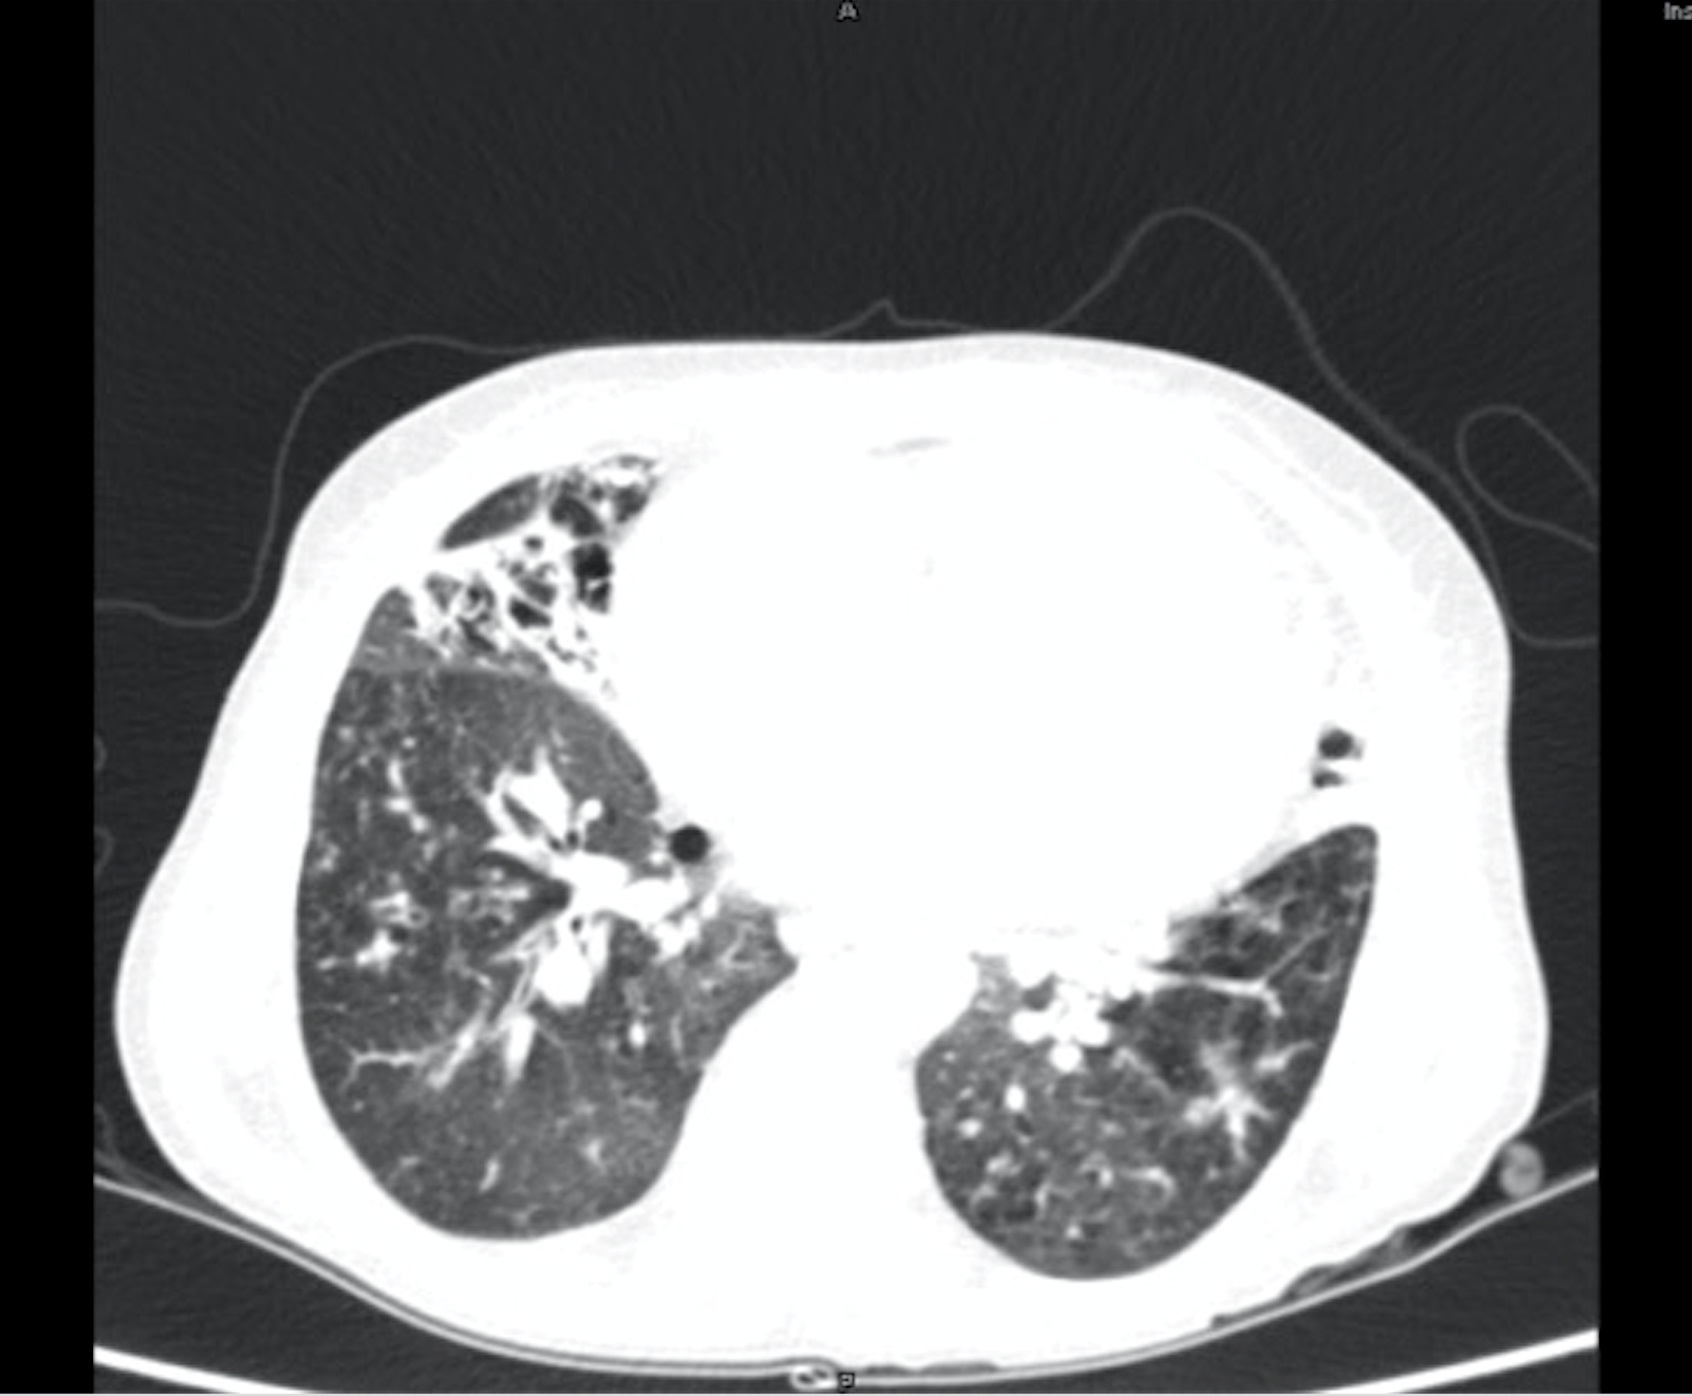

For further evaluation, a contrast-enhanced CT scan of the thorax was done, which revealed varicose bronchiectasis involving the right middle lobe [Table/Fig-2,3] and lingular bronchiectasis of the left upper lobe [Table/Fig-4]. Brochoscopic alveolar lavage fluid was sent for analysis, which grew strains of Mycobacterium avium complex (MAC). A 2D ECHO was done, which showed evidence of severe pulmonary artery hypertension and gross tricuspid regurgitation, with good right ventricular function. Also, the patient was asked if she had the habit of voluntarily suppressing cough, to which her response was affirmative. She was a habitual cough suppressor, as a mechanism to prevent episodes of upper abdominal pain on recurrent cough episodes. With all these findings observed, we concluded that it was a case of ‘Lady Windermere Syndrome’. We started the patient on a 3-drug regimen (rifampicin, ethambutol and clarithromycin). After 2 months of follow up, the patient’s symptoms had slightly improved [Table/Fig-5].

CECT thorax showing right middle lobe bronchiectasis.

CECT thorax showing middle lobe bronchiectasis.